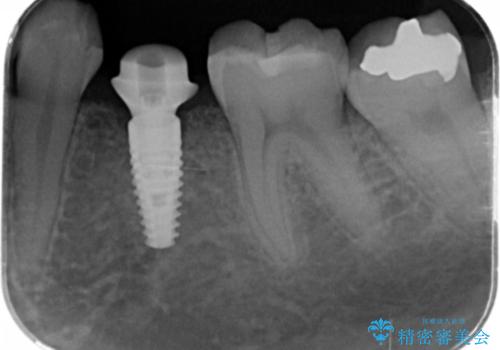

- 大人になっても残存していた乳歯がグラグラし、痛くて噛めない 抜いて欲しいとの希望で来院されました。

歯根が吸収し残すことのできない乳歯を抜去後、隣の歯を削らずに済むインプラント治療で咬合機能の回復を計画します。